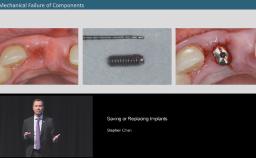

Surgical Planning and Procedures

Saving or Replacing Implants

Congress Lecture